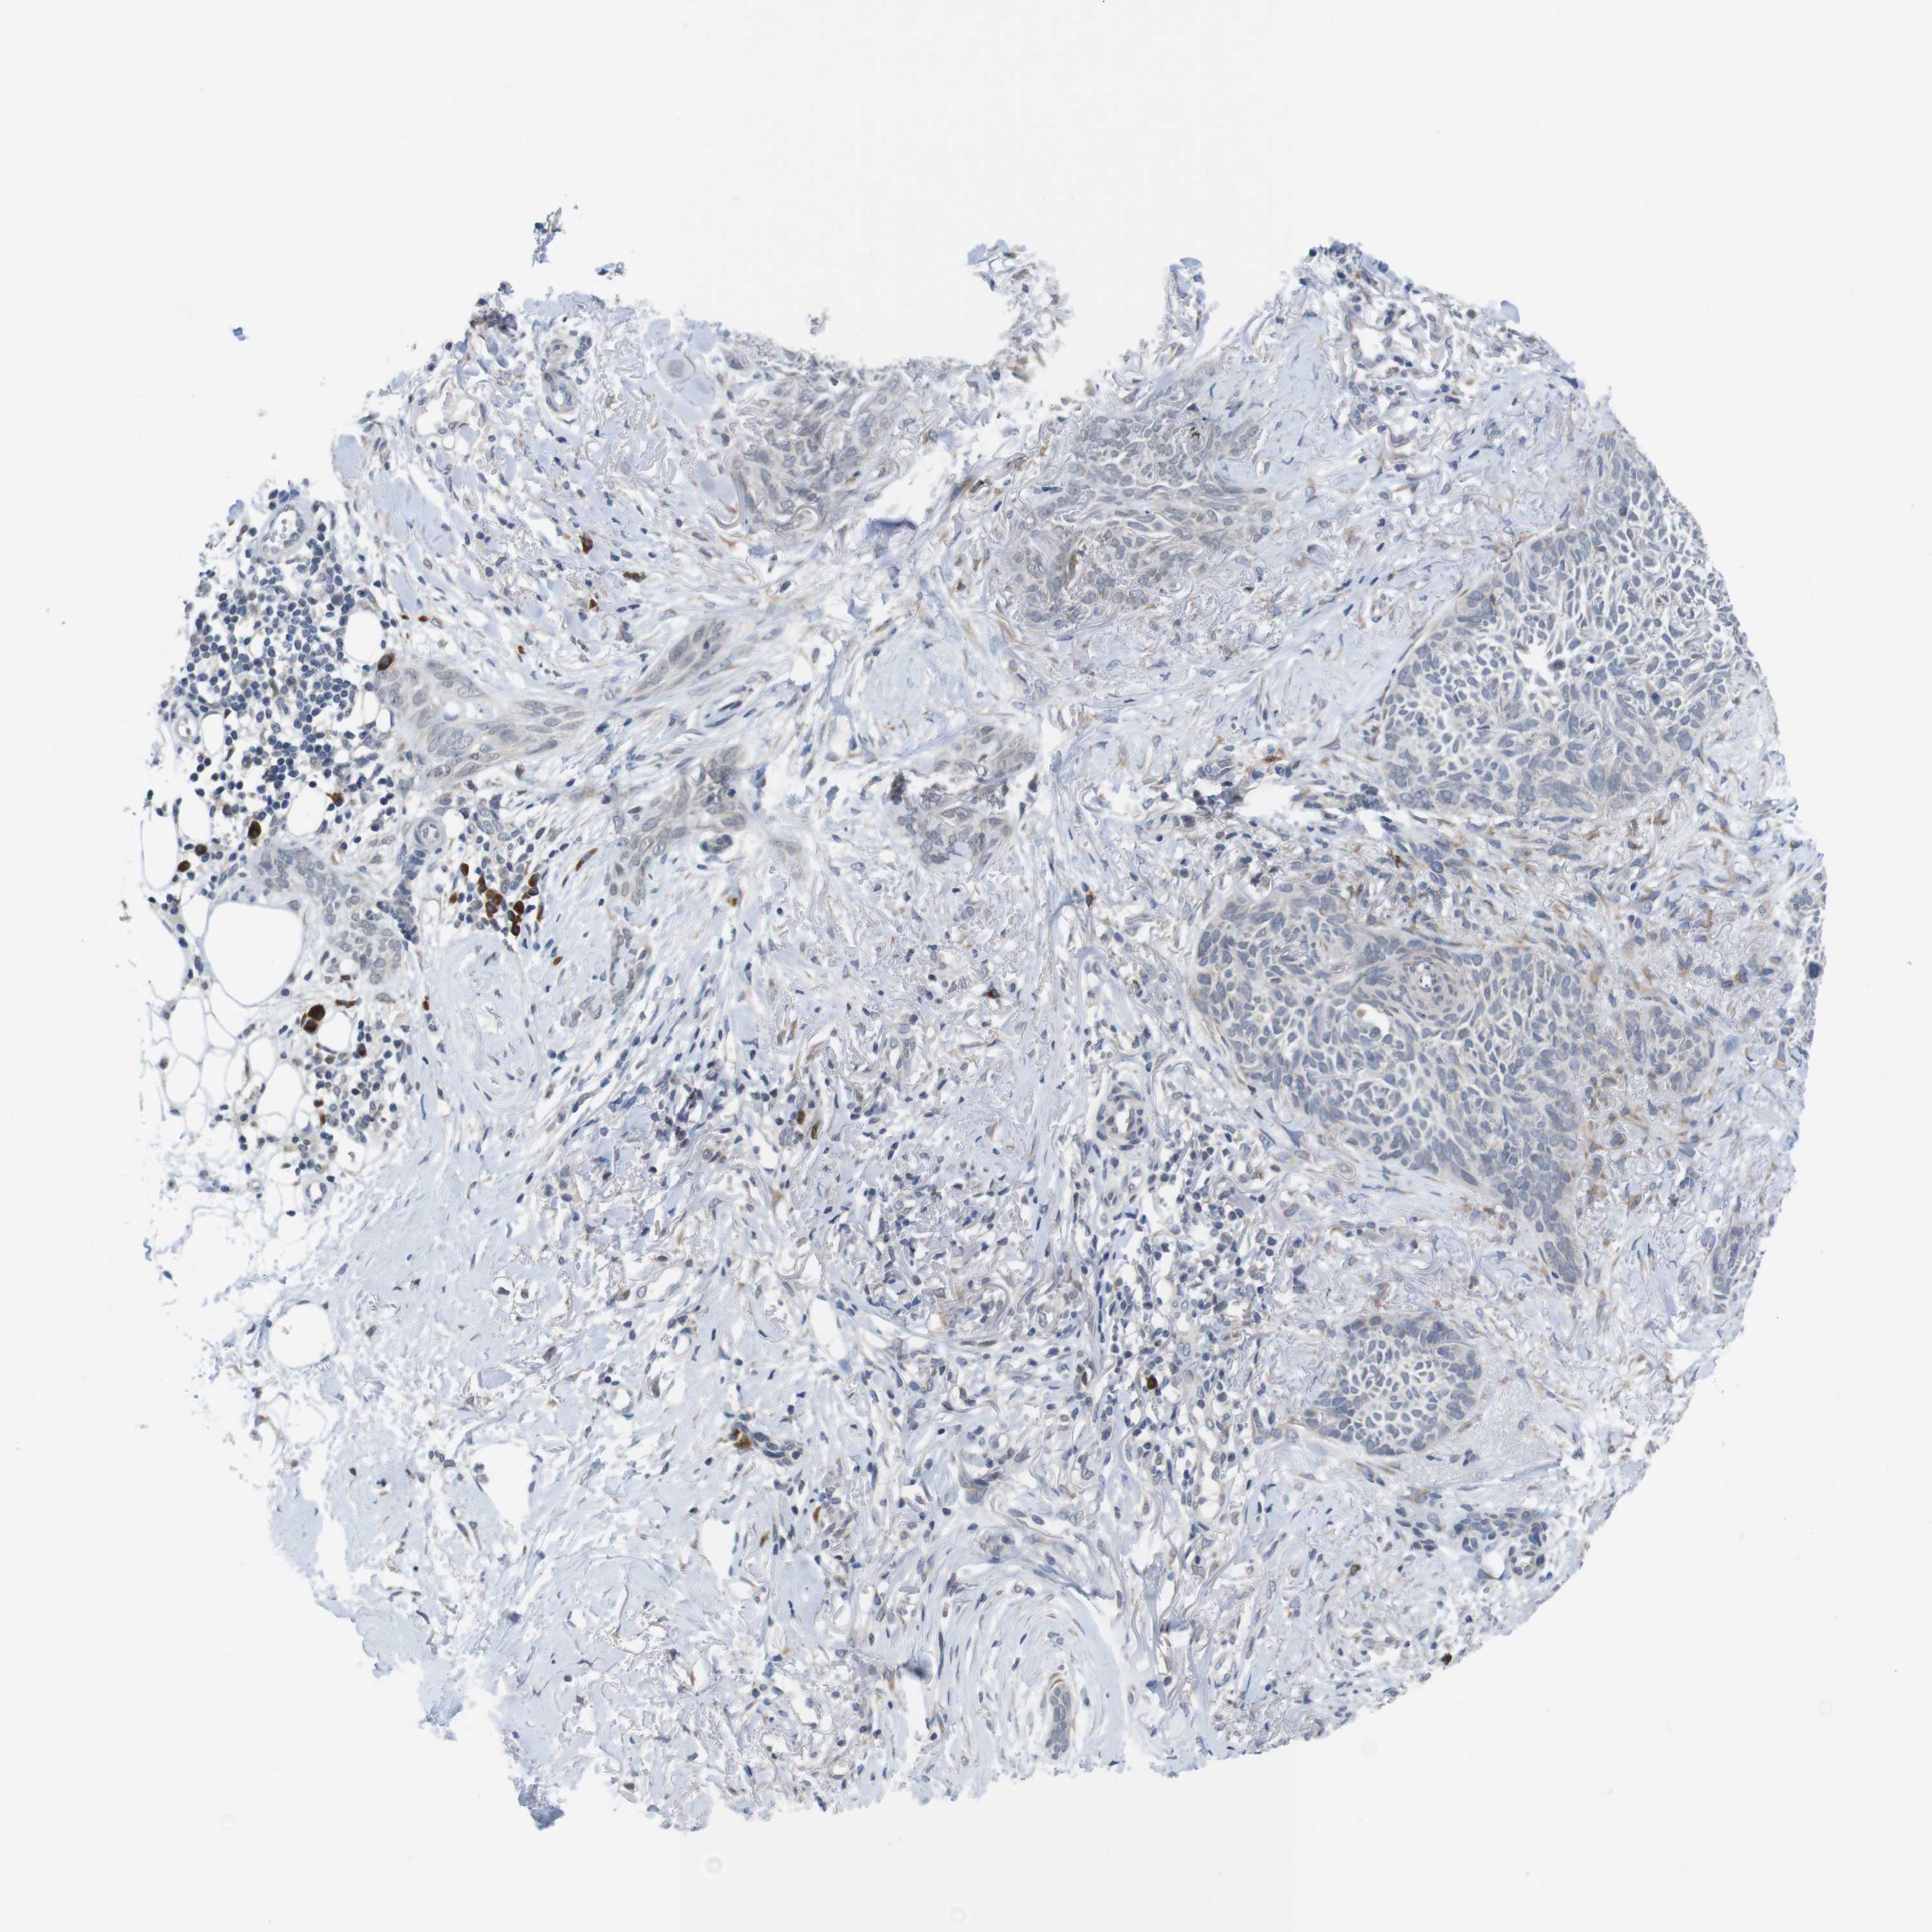

SKIN CANCER - Protein expressioni

A mouse-over function shows sample information and annotation data. Click on an image to view it in a full screen mode. Samples can be filtered based on level of antibody staining by selecting one or several of the following categories: high, medium, low and not detected. The assay and annotation is described here.

Antibody stainingi

Antibody staining in the annotated cell types in the current human tissue is reported as not detected, low, medium, or high, based on conventional immunohistochemistry profiling in selected tissues. This score is based on the combination of the staining intensity and fraction of stained cells.

Each image is clickable and will lead to virtual microscopy that enables deeper exploration of all samples and also displays staining intensity scores, fraction scores and subcellular localization as well as patient and tissue information for each sample.

Squamous cell carcinoma, NOS

Squamous cell carcinoma, metastatic, NOS

Basal cell carcinoma

Squamous cell carcinoma in situ, NOS

Adnexal tumor, benign